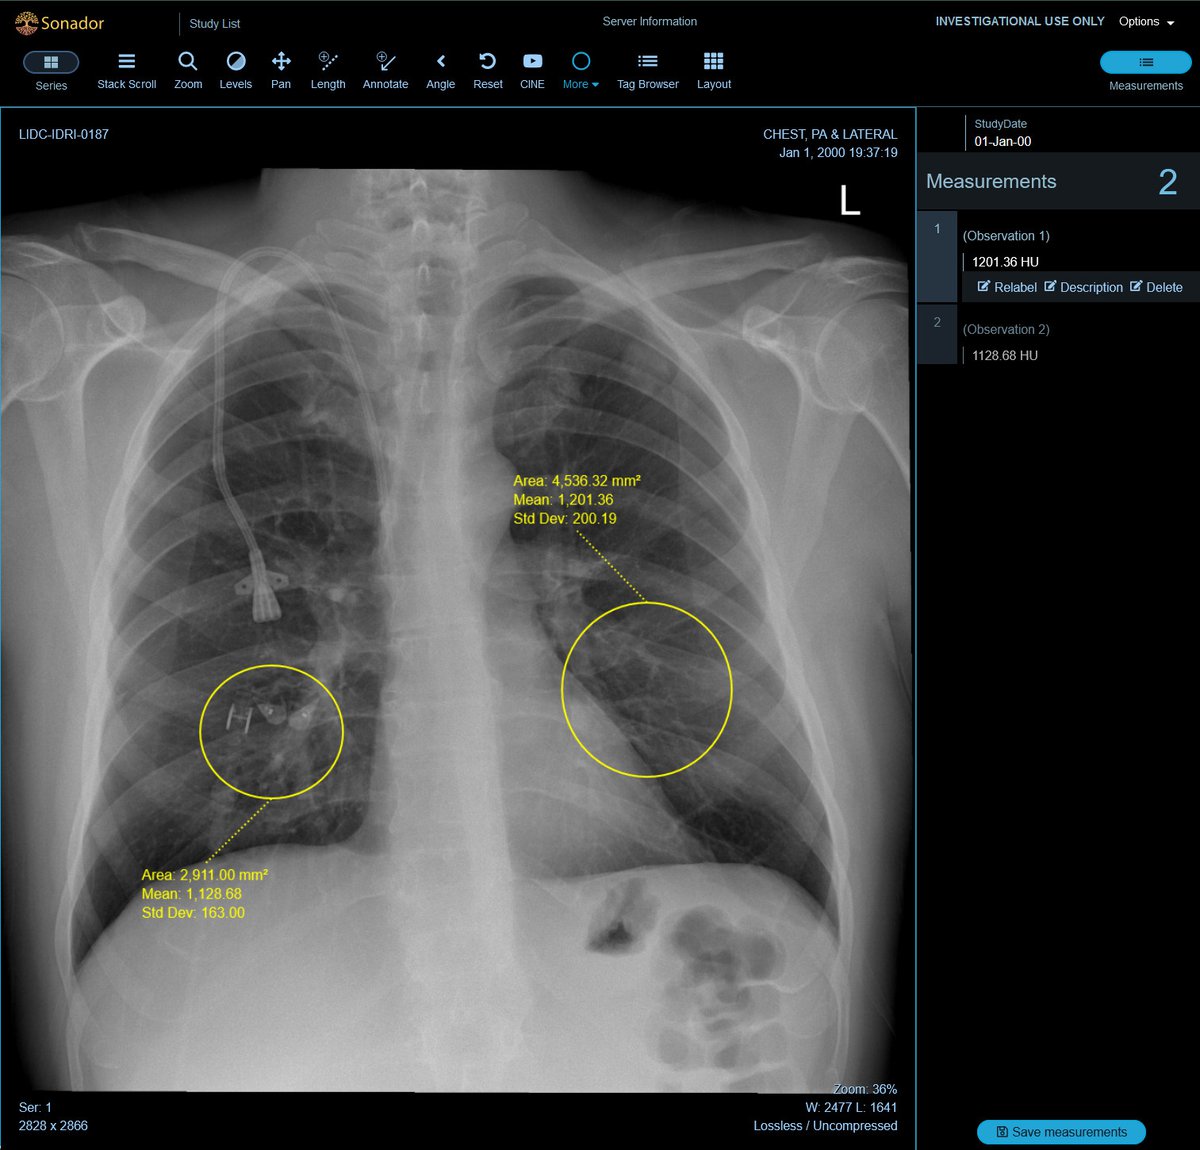

To streamline labeling and review tasks, OHIF provides a powerful set of annotation tools to capture measurements, findings, or other features of interests. The annotations can be paired with the original study and saved as DICOM-SR documents and sent back to Orthanc, enabling them to be transferred along with the source images for downstream processing.